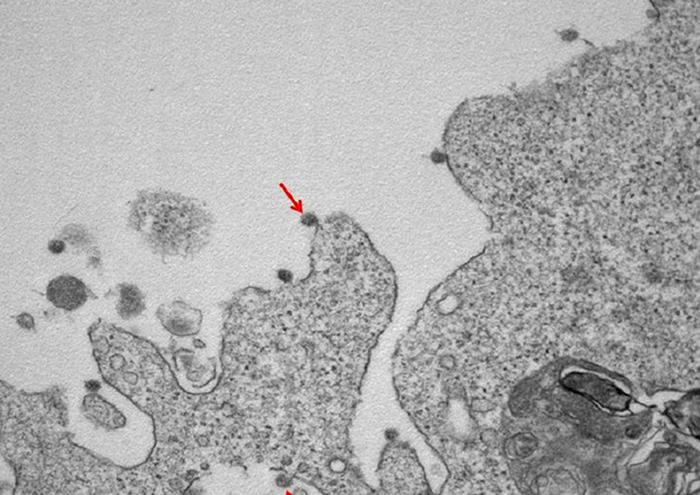

(ANSA) – MILANO, 02 APR – Si vede anche la famosa ‘corona’, nel primo ritratto in bianco e nero del virus SarsCoV2 isolato in Lombardia all’Ospedale Sacco di Milano: le immagini al microscopio elettronico mostrano le particelle virali attaccate alle membrane delle cellule e la loro tipica corona di glicoproteine superficiali.

Nella prima, a un ingrandimento di 30000X, si osservano le particelle virali di SarsCov2 (indicate dalle frecce), adese alle membrane sulla superficie e all’interno di cellule utilizzate per l’isolamento.